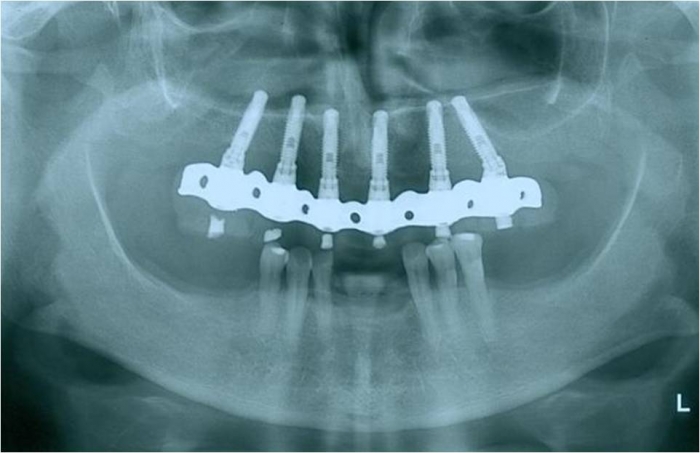

Raio X dos Implantes Instalados